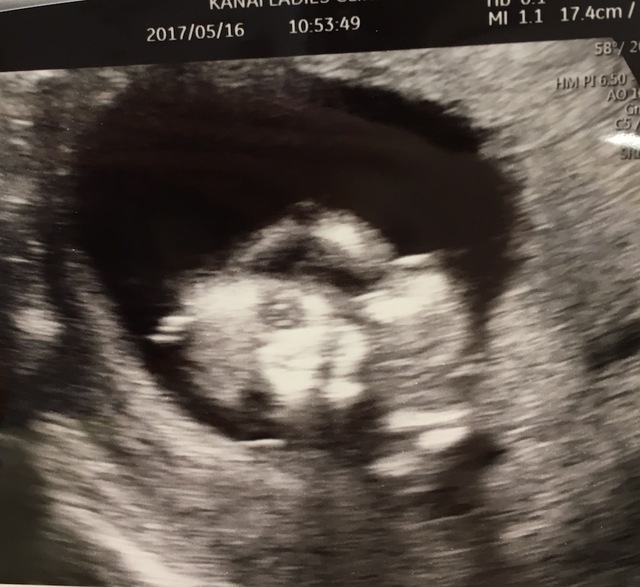

15週3日(15w3d・男の子)|kaaaa さん(25歳)

エコー写真撮影時のエピソード:

第二子にして初めて4Dエコーを貰った時のものです。まだ4ヶ月で胎動もなく今まで3Dエコーではぼんやりとした輪郭しか分からなかったのにちゃんと人の形になってる!!と感動しました。

主人も今まではエコーを見ても「ふーん」ぐらいの素っ気ない返事でしたが、これには喜んでくれました!やっぱり見やすい方が実感湧くのでしょうか。(笑)

上の子もまだ1歳でしたが、この頃から「ママのお腹には赤ちゃんがいるんだよ~~。こんなして寝んねしてるよ~~。」と話していました。毎日お腹をさすってくれて産まれる前からお姉ちゃんをしてくれています。